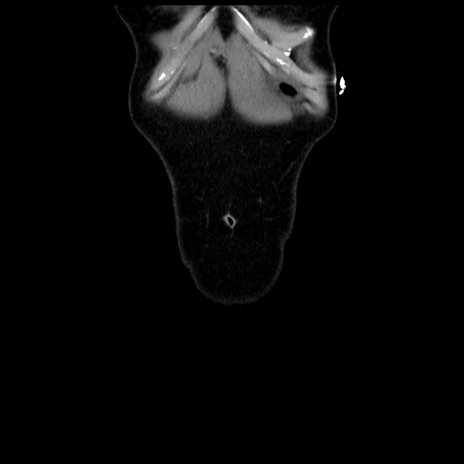

矢状断像

【症例】 50歳代女性

【主訴】 腹痛

【現病歴】前日生レバーを食べた。今朝に排便あり。 昼前に突然発症の腹痛を生じ、当院救急外来を受診した。

【既往歴】 子宮筋腫にてで子宮全摘後

【身体所見】 意識清明、腹部:平坦、軟、下腹部やや左を中心に圧痛・反跳痛あり、筋性防御あり

【データ】WBC 7800、CRP 0.07